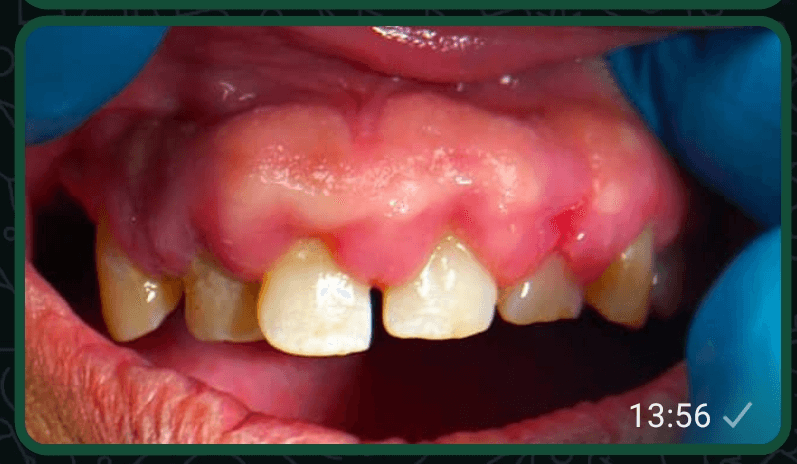

SWOLLEN MOUTH WITH BLOOD STAINS DISAPPEARED

For about a year, anytime i brush my teeth, blood will drop from my mouth. This was because my mouth was swollen.

This was happening at least 3 times every weak. Even when i am eating, i will feel pains in my mouth. 2 months ago, i saw an advert about these products and decided to buy them. After using them for 1 week, the swelling disappeared.

I also stopped seeing blood in my mouth and all the pains stopped.